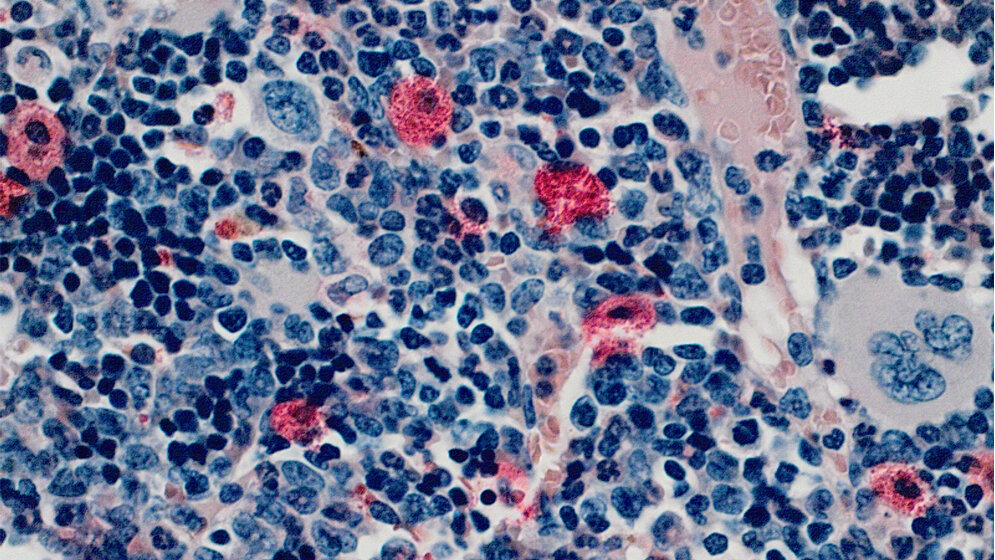

Chronische myeloische Leukämie (CML) entsteht durch bösartige Veränderungen von blutbildenden Zellen des Knochenmarks und tritt meist bei älteren Menschen auf. Etwa 20 Prozent der Leukämie-Erkrankten im Erwachsenenalter leiden an dieser Art Blutkrebs. Das Protein Gab2 wirkt als Verstärker von krebserregenden Signalen und liegt bei CML oft in höherer Menge vor als in gesunden Zellen üblich. Freiburger Forschende haben in zwei Studien neue Erkenntnisse dazu gewonnen, wie CML und Gab2 zusammenhängen und welche Medikamente eine bestimmte Resistenz von Gab2 bei CML brechen können.

Darüber hinaus wiesen die Forscherinnen und Forscher die wichtige Rolle von Gab2 bei der Entstehung und Ausbreitung der CML nach. In einem Mausmodell, in dem durch Einbringen von Bcr-Abl im Knochenmark die CML-Entstehung nachvollzogen werden kann, führte ein Mangel an Gab2 zu deutlich abgeschwächten oder ausbleibenden Krankheitssymptomen. Dies zeigt, dass Gab2 für die Entwicklung und das Fortschreiten der Krankheit zentral ist. Zukünftig könnten Ärztinnen und Ärzte Gab2 daher als Biomarker verwenden, also mithilfe einer Gab2-Messung darauf schließen, wie die Krankheit verlaufen wird. Außerdem könnte Gab2 als neues therapeutisches Angriffsziel in der Behandlung der CML dienen. (idw, red)